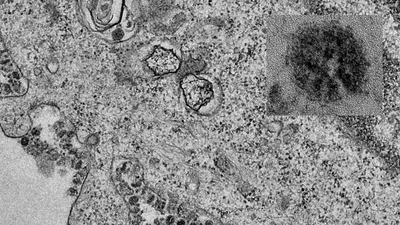

(PLO)- Thông tin từ Trung tâm đáp ứng khẩn cấp các sự kiện y tế cộng đồng, Bộ Y tế, cho biết đến 6 giờ ngày 1-2, đã có 11.302 người mắc bệnh. Trong đó tại Trung Quốc là 11.145 người mắc. Có 258 người đã tử vong do virus Corona.